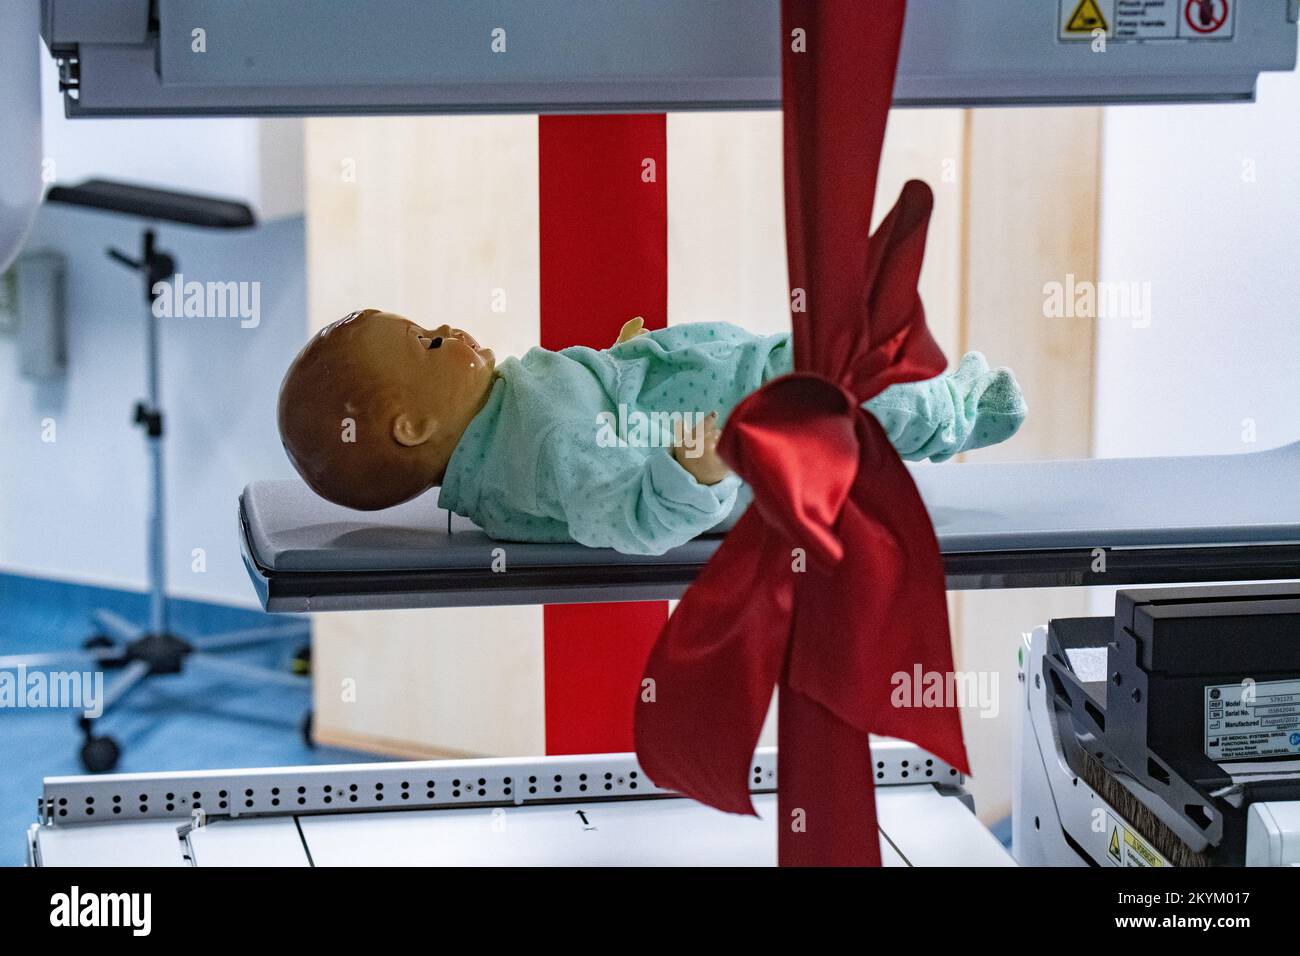

RM2KYM017–01 décembre 2022, Mecklembourg-Poméranie occidentale, Greifswald: Un dispositif NM/CT 870 DR de General Electric Medical Systems, Israël est sur le point d'être remis dans les salles de la clinique pédiatrique du centre médical de l'université de Greifswald. Ce système SPECT/CT permet des examens médicaux nucléaires encore plus précis. Ceci est nécessaire pour les options de traitement spéciales telles que la thérapie par radio-isotope. La tomodensitométrie (CT) utilise un grand nombre d'images radiologiques pour calculer les images numériques. Une acquisition SPECT, en revanche, utilise une caméra gamma pour rendre visible le faible rayonnement des médicaments radioactifs. Dans cette

RM2KYKWRY–01 décembre 2022, Mecklembourg-Poméranie occidentale, Greifswald: Une unité NM/CT 870 DR de General Electric Medical Systems, Israël est sur le point d'être remise dans les salles de la clinique pédiatrique du centre médical de l'université Greifswald. Ce système SPECT/CT permet des examens médicaux nucléaires encore plus précis. Ceci est nécessaire pour les options de traitement spéciales telles que la thérapie par radio-isotope. La tomodensitométrie (CT) utilise un grand nombre d'images radiologiques pour calculer les images numériques. Une acquisition SPECT, en revanche, utilise une caméra gamma pour rendre visible le faible rayonnement des médicaments radioactifs. Dans cette wa

RM2KYM014–01 décembre 2022, Mecklembourg-Poméranie occidentale, Greifswald: Un panneau avec les mots «Telemedically Integrated, German-Polish Pediatric cancer Center dans l'Eurorégion Pomerania» est accroché derrière un dispositif NM/CT 870 DR de General Electric Medical Systems, Israël dans les salles de la clinique pédiatrique du centre médical de l'université Greifswald. Ce système SPECT/CT permet des examens médicaux nucléaires encore plus précis. Ceci est nécessaire pour les options de traitement spéciales telles que la thérapie par radio-isotope. La tomodensitométrie (CT) utilise un grand nombre d'images radiologiques pour calculer les images numériques. Une acquisition SPECT, sur t